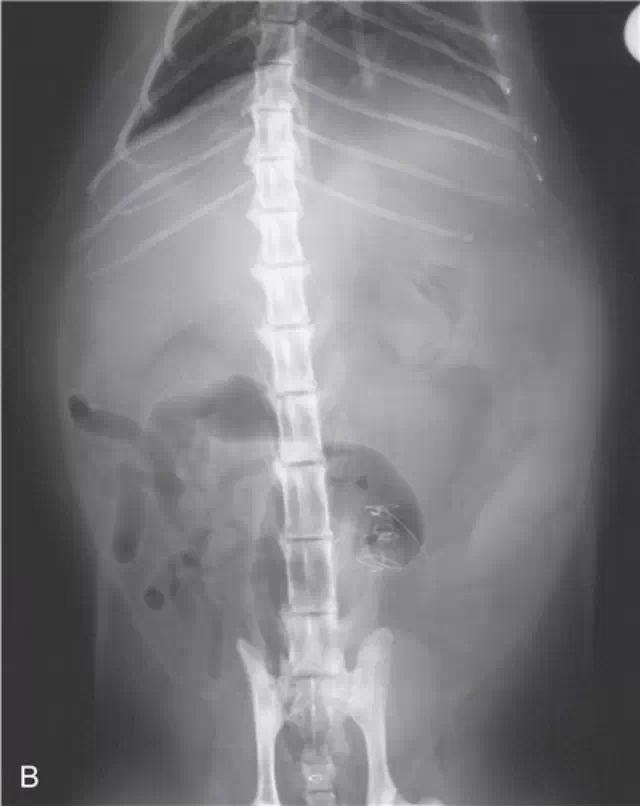

肝脏x线片判读 肝肿大 艾贝尔兽医学院 微信公众号文章阅读 Wemp